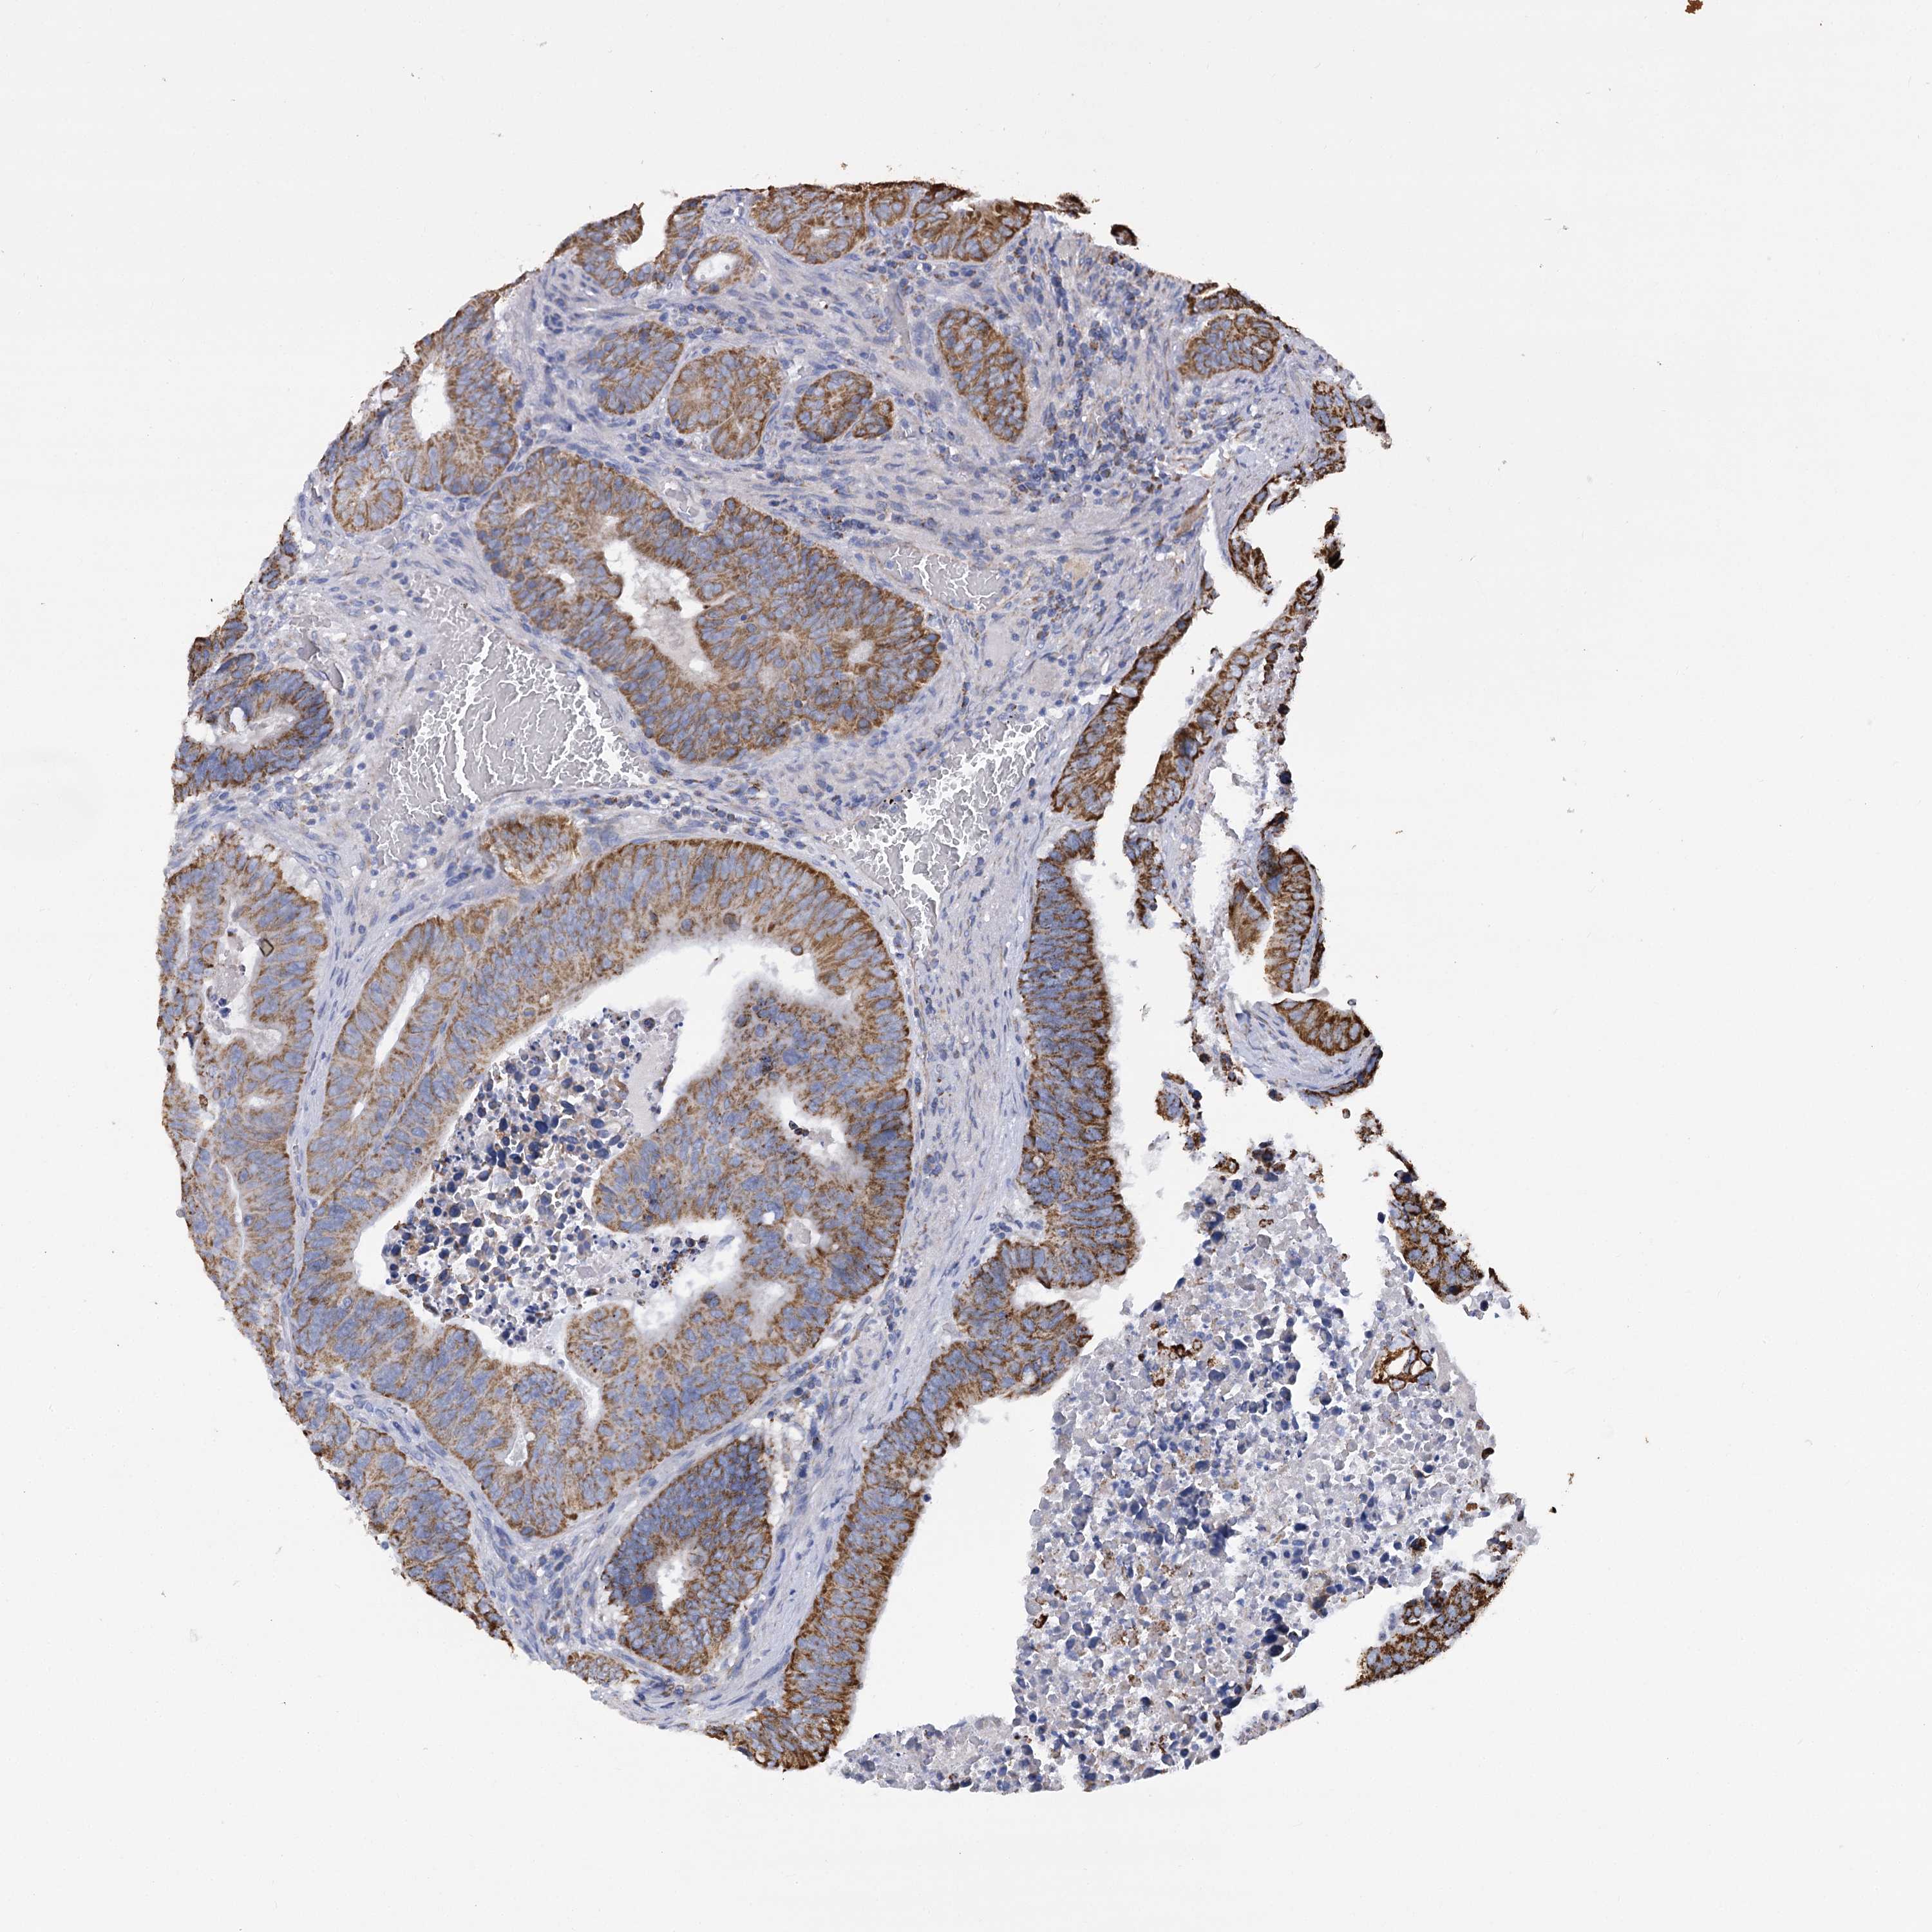

CANCER COLORECTAL CANCER Show tissue menu

Colorectal cancer

Human cancer

Colon adenocarcinoma

Rectum adenocarcinoma